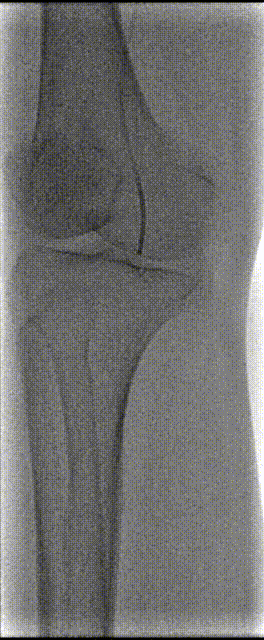

1,患者取平卧位,术区常规消毒、铺单。2%利多卡因局部麻醉满意后,逆行穿刺左侧股总动脉成功后置入血管鞘,经鞘管造影证实在股总动脉,全身肝素化。沿左侧鞘管置入超滑导丝及MPA1导管,导丝、导管配合“翻山”超选进入右髂总动脉,造影见:右髂外动脉、股总动脉、股浅、股深动脉显影良好,腘动脉收肌管部以下及膝下动脉未见显示。